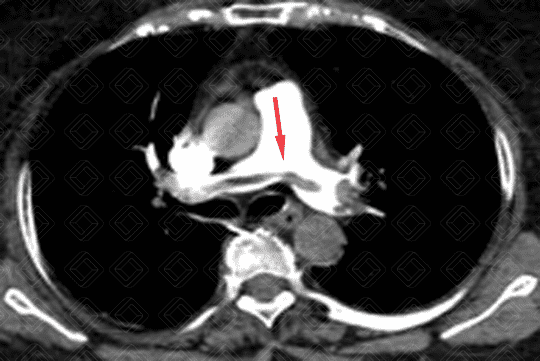

Descrição das imagens: Angiotomografia computadorizada do tórax com aquisições axiais e coronal, evidenciando tromboembolia pulmonar maciça com “êmbolo em sela” (seta vermelha) nas artérias pulmonares principais.

• Angiotomografia computadorizada do tórax: Padrão-ouro para o manejo do TEP agudo. Este exame é sempre realizado após a administração do meio de contraste. O principal sinal é a falha de enchimento, formando um ângulo agudo com a parede do vaso, delimitada pela substância contrastante (figura 1).